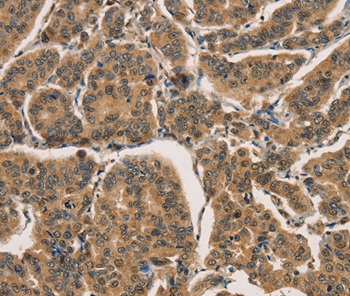

Immunohistochemical analysis of paraffin-embedded Human breast cancer tissue using #36377 at dilution 1/30.